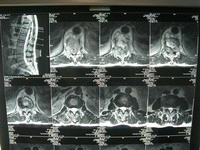

1.男女性別發病率明顯差別,多見於青壯年全身症狀多不明顯。發病部位以胸椎最為常見,次為腰椎和頸椎。病變多在胸椎椎弓三面環繞脊髓,脊髓受壓來自後側,為此25%~50%病例並發截癱,比椎體結核並發截癱的頻率高;除患處疼痛外神經根放射痛也較為常見。

2.病變接近體表,病程較脊椎結核者短,近脊柱中線,常出現腫塊、膿腫或竇道。脊柱無畸形、活動無明顯受限。